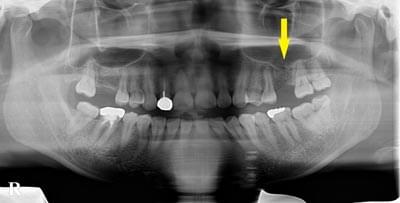

患者様のインプラント治療前のレントゲン写真です。右下顎大臼歯2本の抜歯後のレントゲン写真で、写真の黄色矢印は、歯の周囲の歯槽骨が大きく吸収されてしまっていました。

骨移植による骨造成について2

写真のように、CTで見ると、骨吸収の様子が良く分かり、下顎骨の中を通る神経近くまで骨がありませんでした。

さらに、CTで、別な方向から見ると、黄色矢印のように骨が吸収されていて、緑色矢印で示される神経の通る管に迫り、インプラントが埋入できるような骨量はありませんでした。